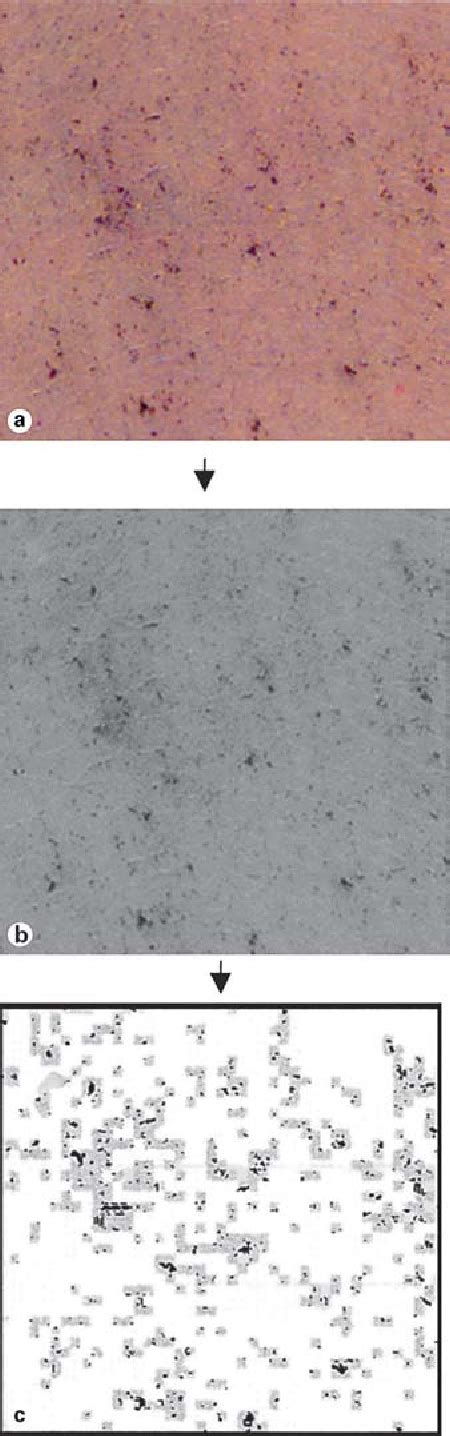

inflammatory response  appendiceal serosa  features  vernix 671×503

inflammatory response appendiceal serosa features vernix